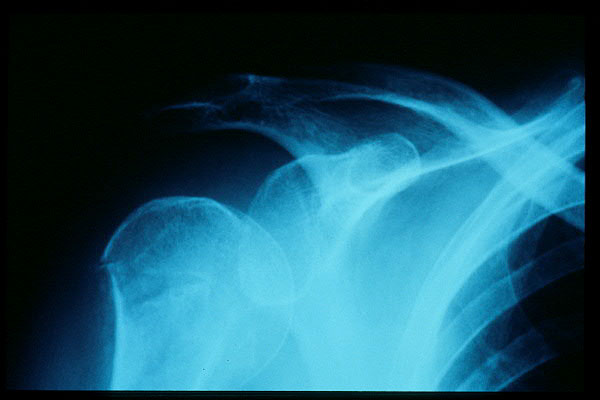

Fractura impactada de húmero .